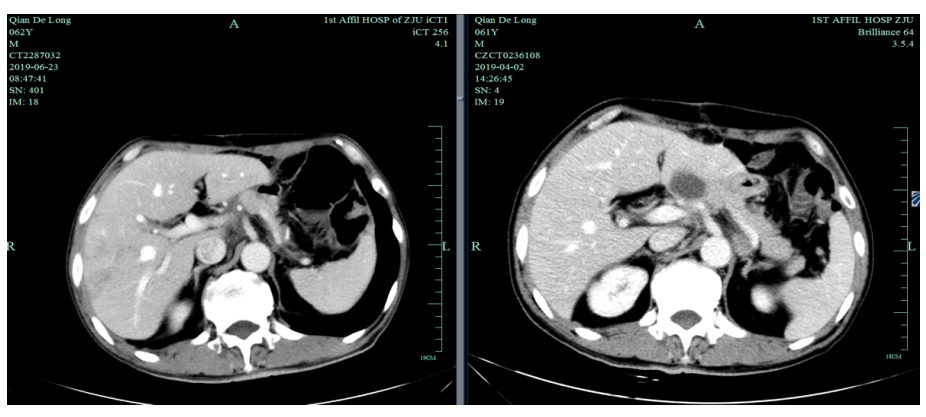

由于奥沙利铂8个周期化疗结束,2019-6-26至2019-11-29行S-1+赫赛汀 q3w 8周期联合维持治疗:替吉奥3# BID D1-14、赫赛汀 300mg D1。

2019-12-20至2020-7-6行SPA+赫赛汀 q3w  8周期联合化疗:白蛋白紫杉醇250mg、替吉奥3# BID D1-14、赫赛汀 300mg D1 。

疗效评估:

2019-12-20至2020-7-6

影像学评估:胃癌术后改变。持续CR。

肿瘤标记物评估:肿瘤标记物明显下降。